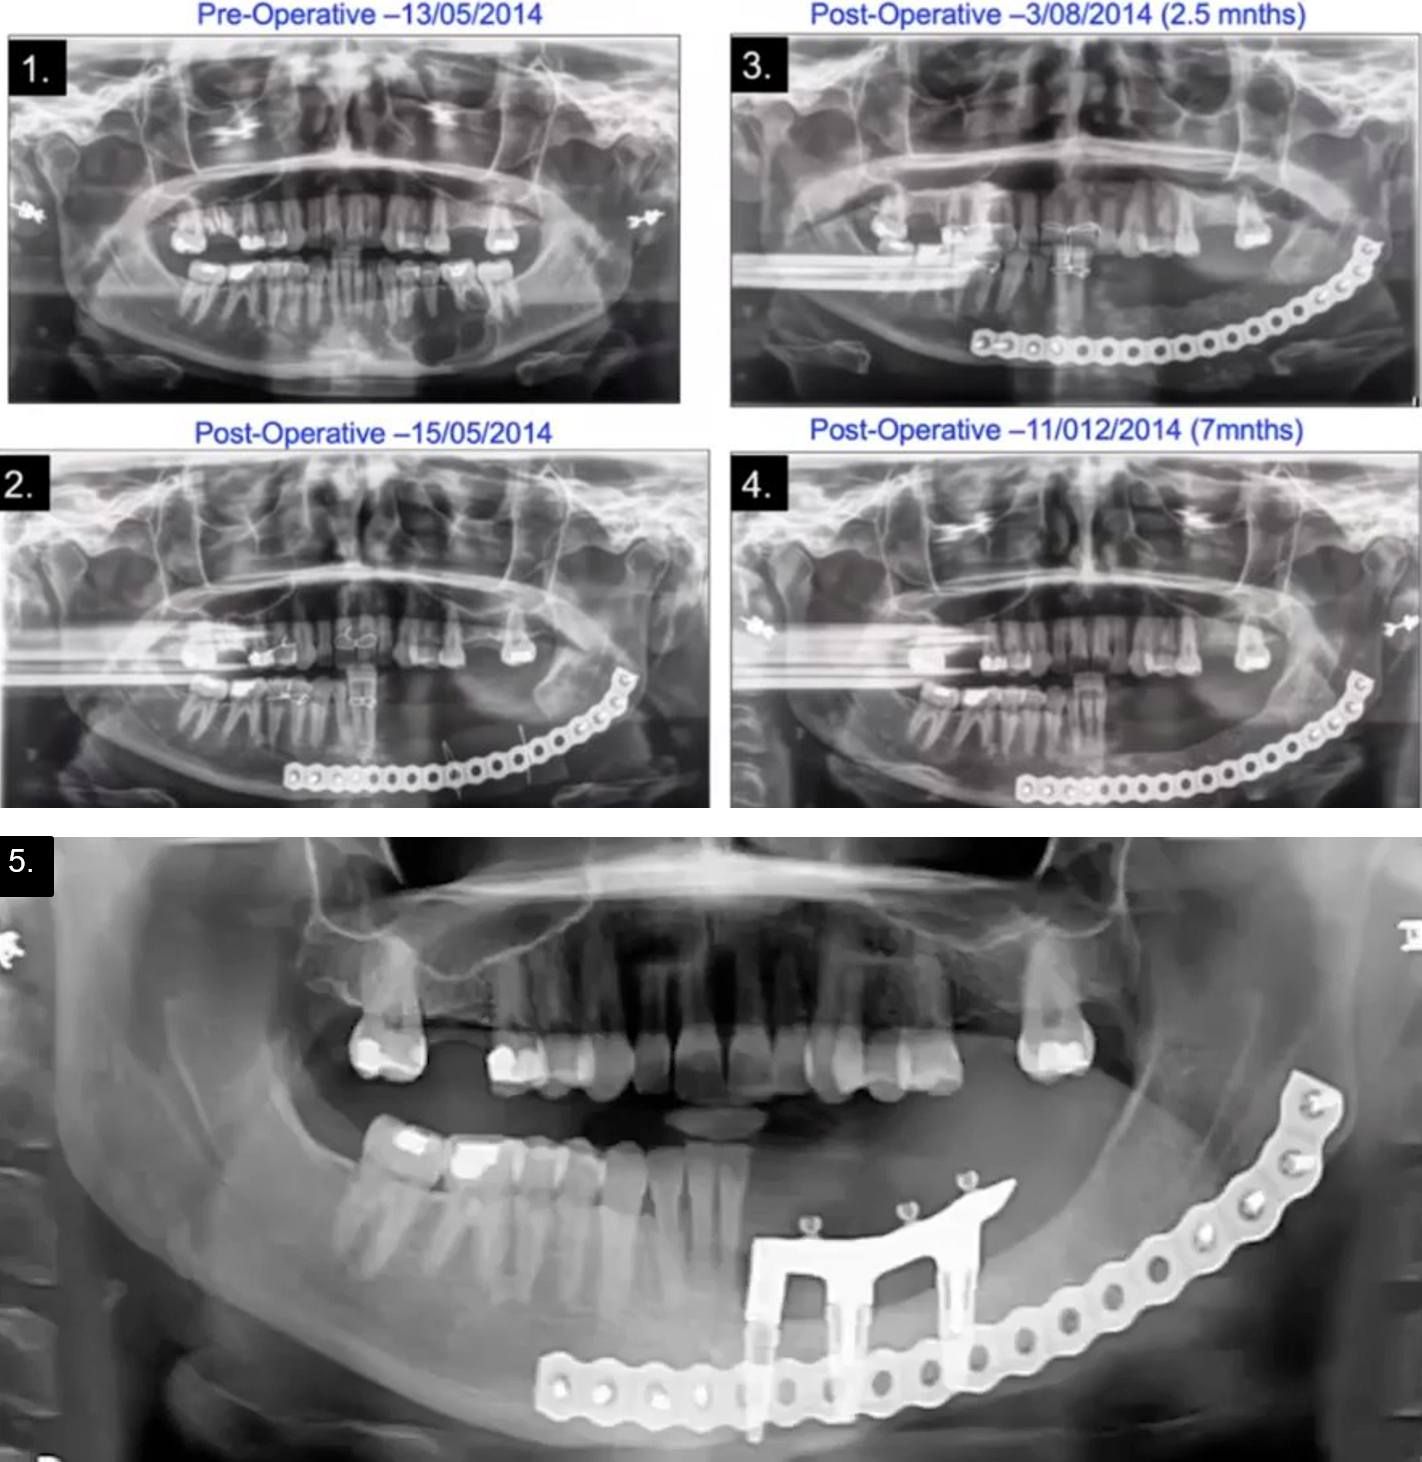

Patient-specific implant placement in an ameloblastoma patient: advantages of 3D technologies in facial surgery

A case with Professor Carlo Ferretti involved a patient with ameloblastoma requiring resection and reconstruction [2]. The 3D virtual planning was very beneficial, as the patient-matched reconstruction plate could be bent on a 3D printed model allowing for the development of cutting guides for the patient-matched plate. The tumor was resected intraorally, resulting in no external incision, and the plate was inserted followed by a silastic spacer with similar anatomy to the part of the mandible removed. Once the defect was closed, the spacer remained in situ for three months, after which it was removed through a small extraoral incision. Compressed particulate cortico-cancellous iliac crest bone was then injected into the pocket left behind after removal of the spacer. The final reconstruction involved implants placed into the graft, a successful procedure accurately executed through the assistance of virtual treatment planning (Figure 1).